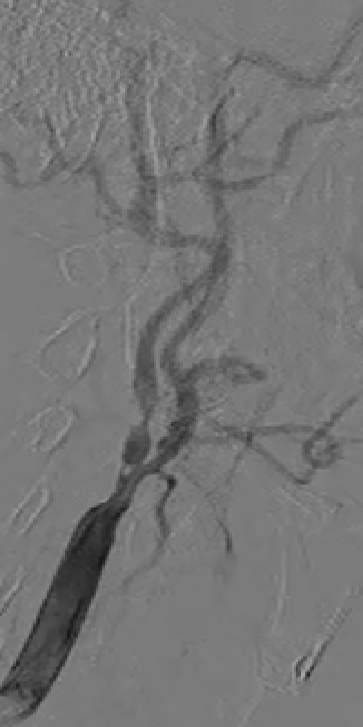

案例1

放完支架后形态和血流通畅,但在做保护伞回收过程中,回收鞘上不去了,表明球囊后扩张可能会取得更好的效果。